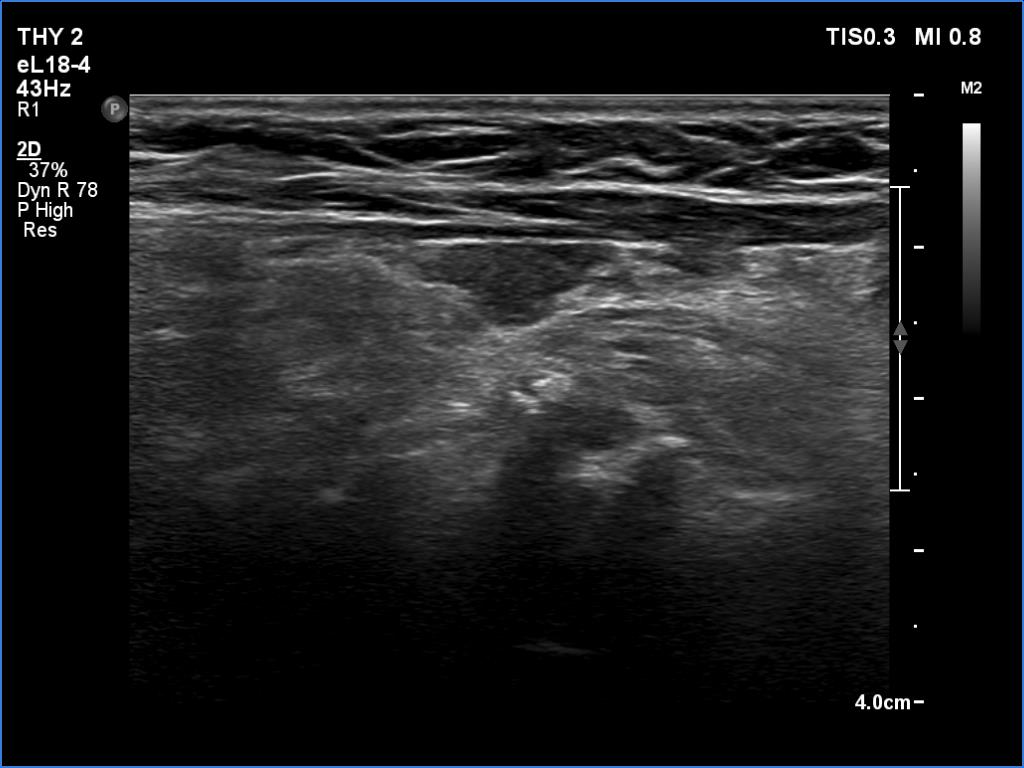

Clinical data: A 64-year-old woman came to a routine follow-up. She has been operated on a multinodular goiter for more than 20 years. A total thyroidectomy was performed. A recent thyroid ultrasound resulted in thyroiditis or recurrent nodule.

Ultrasonography. Great part of the lobes was composed of hypoechoic mass which showed irregular shape.

Overwhelming majority of the operated thyroids became hypoechoic.

This is one of the characteristic presentations of an operated thyroid, a lobe is partly hypoechoic partly echonormal.